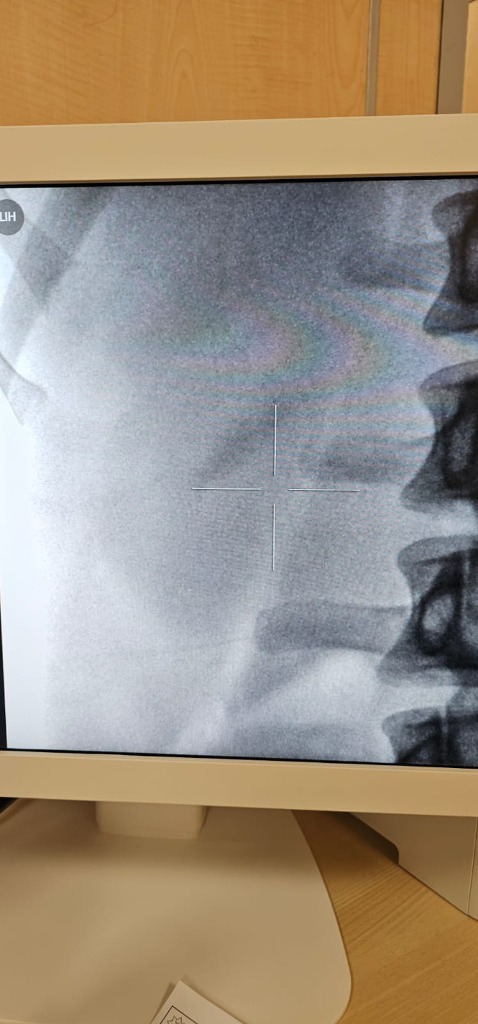

After ESWL X-ray

After